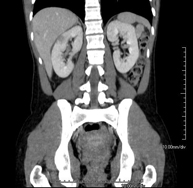

- Kidney CT

Diagnostic test that involves obtaining high-definition anatomical two- and three-dimensional images of the kidney and urinary system using CT (computed tomography) equipment. The study is performed before and after the use of iodinated contrast in different ‘renal phases’ for functional and anatomical assessment (renal parenchyma, ureters, urinary bladder, renal arteries and veins, etc.), as well as adjacent structures (inferior vena cava, abdominal aorta, liver, spleen, etc.). It is particularly recommended when kidney damage is suspected, in patients with blood in their urine or haematuria, etc.